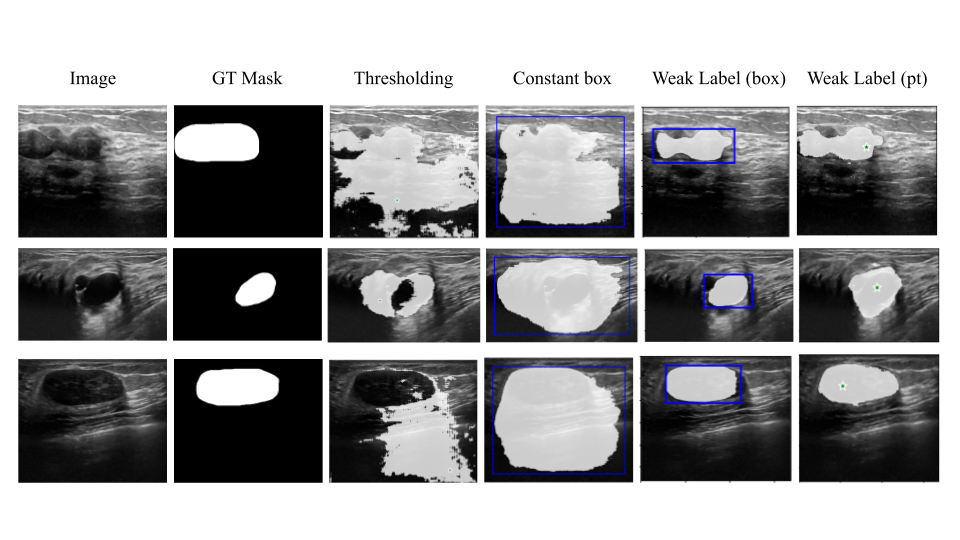

Refer to caption

Figure 1: Labels obtained from different configurations of SAM and MedSAM. Our method auto-generates effective input prompts (bounding boxes) using only very few annotations to generate high quality weak labels while SAM and MedSAM fail in auto options and are sensitive to input prompts in manual option.

Intuitively, MedSAM should help us annotate the unlabeled images out-of-the-box and obtain labels to augment our training dataset. However, one major limitation of SAM and MedSAM is their sensitivity to input prompts. Both models are only as good as the point or box inputs they receive on a given image. In specific, for medical images, the area of interest to be segmented may be particularly subtle within the image with thin fine-grained boundaries. Also, inputs that include too much of the target or background result in over- or undersegmentation, requiring precise input prompts to get a good segmentation. This can be seen in Fig. 1, where we show labels generated from SAM and MedSAM. MedSAM clearly gives us better labels than SAM, but it is very sensitive to the bounding box prompt we use and is still constrained by the manual prompting part. We also note that auto-prompting MedSAM performs poorly and often leads to blank segmentation predictions. Therefore, selecting an appropriate input prompt is key to ensuring success. Also, eliminating the need for manual prompting could allow practitioners to auto-generate labels for any number of unlabeled real or synthetic data, which would be very useful in label-scarce scenarios.